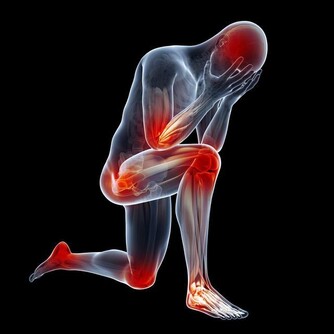

但從西醫的角度來講,腰痛更多的可能是感染,還有就是是結石,當然過於疲勞也可能會發生腰痛。

此外,外部損傷也是腰痛的一個重要原因。骨頭損傷最常見的就是椎間盤突出滑脫,多發生在很多人彎腰提起重物的時候。

上了年紀的人,特別容易引起骨質增生,這些情況都可以引起椎間盤損傷、脫出甚至是裂開。這也是常見的腰痛。

腰痛在泌尿外科,最多見的是結石和泌尿系感染這兩種。特別厲害的腰痛,我們稱之為“腎絞痛”。

一般不太厲害的腰痛,就覺得腎區有點悶痛,或者體表位置引起疼痛,這就要看具體病人的表現。

可見,腰痛既是一個小問題,也是一個大問題,不能忽視。